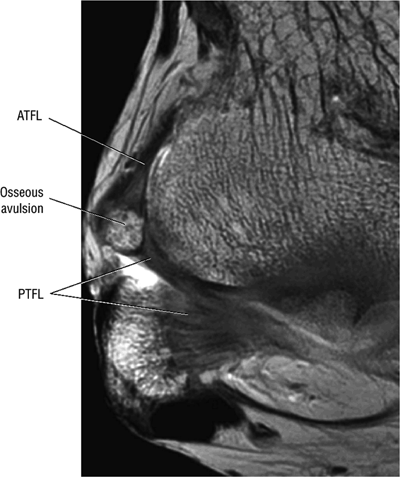

The ATFL is found on sagittal images one slice central to the lateral-most sagittal slice that includes the lateral malleolus. The origin of the ATFL is seen at the anterior inferior tip of the lateral malleolus. The anteromedial course of the ATFL can be followed on the next two images moving centrally, to where it inserts on the talus.

-

The posterior talofibular ligament (PTFL) is located in a similar fashion. The origin of the PTFL is at the inferior tip of the lateral malleolus, and the tendon can be followed medially to its insertion on the mid-posterior aspect of the talus. The PTFL is seen in cross-section on sagittal images and has a cord-like appearance. Posterior to the talus, this cord-like appearance should not be mistaken for a loose body in the posterior joint.